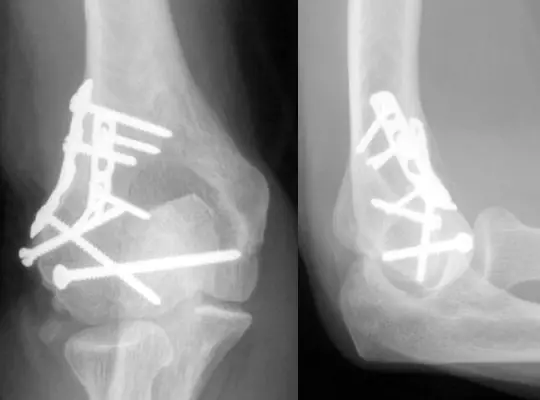

عمليات الشرائح والمسامير، من المعروف أن كل الأشخاص معرضون للكسر في أي وقت ففي الحالات البسيطة يتم علاجها بالجبيرة، ولكن في الحالات المعقدة منها تحتاج إلى تركيب الشرائح والمسامير من أجل ضمان ثباتها والتئامها بالشكل الصحيح.

حيث تساعد الشرائح والمسامير على التئام حالات الكسر بطريقة طبيعية واستقرار العظام في أماكنها الصحيحة ويقوم جسم المصاب بتقبل وجودها حيث لا يتعامل معها على أنها جسم غريب.

- حدوث الكثير من حالات الكسر متعددة الشظايا في العظام، حيث يتم إجراء الجراحة لإزالة القطع العظمية المتكسرة وتنظيف مكان الإصابة.

- الكسور المصحوبة بإصابات في الأوعية الدموية وفي الأربطة أو العضلات.

- الكسور الناتجة عن حوادث عنيفة والتي تسبب أضرار معقدة.

- في حالات الكسور غير المستقرة، حيث لا تبقى العظام في وضعها الطبيعي دون تثبيت.

- عندما يكون الكسر قريبًا من أحد المفاصل، قد يتسبب ذلك في تلف المفصل أو الأنسجة المحيطة به.